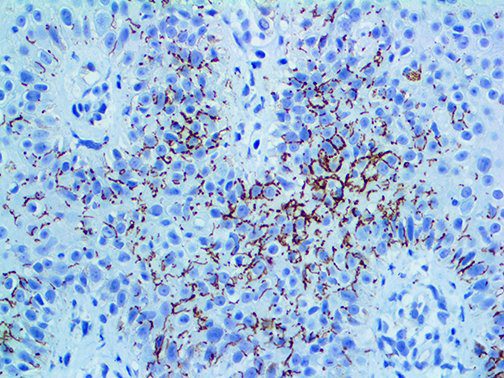

This activation induces inflammatory monocytes to highly express IL-6, starting a localized and then systemic cascade effect that results in hyperproduction of IL-6, which accelerates the inflammatory process. Because IL-6 also increases vascular permeability, excessive levels cause blood vessels to become very leaky. This, along with clotting factors released from vascular endothelial cells, stimulates the coagulation cascade, resulting in microthrombosis (tiny clots), which leads to ischemia and tissue death of the kidney, intestines, heart, liver, brain and extremities.